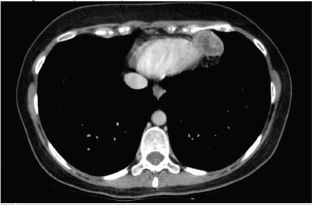

In December, she noticed a round mobile palpable mass in the left axilla, measuring 2–3 cm. Ultrasound features were consistent with sebaceous cyst (Figure 2). In January 2016, she underwent tumour resection. Immunohistochemical study revealed the expression of desmin and smooth muscle actin in neoplastic cells, which was compatible with metastatic leiomyosarcoma. In April 2016, routine mammography associated with breast ultrasonography showed an ovoid hypoechoic nodule, with absence of flow on Doppler image, located in the retromammary/subaponeurotic fat plane, in the upper lateral quadrant of the right breast, category BI—RADS 3 (Figure 3). During the same period, a painful, mobile, palpable mass with ill-defined borders was noticed in the left arm. A new surgical resection of both masses was performed in May 2016 with histopathology confirmation of metastatic leiomyosarcoma. The patient underwent 18F-FDG PET/CT in June 2016 showing no metabolic changes or any suspected lesions. In January 2017, eight months after the last surgery, an asymptomatic mass was found in the pericardial fat (Figure 4) and another mass appeared in the right subcutaneous tissue of the breast (Figure 5). Since there was a risk of growth of the mass in pericardial fat tissue with compression of the heart, first-line chemotherapy was initiated and doxorubicin was scheduled to be administered every three weeks. After three cycles of chemotherapy, restaging CTs revealed that both masses had grown slightly. Thus, a videothoracoscopy was performed in May 2017 for the resection of the mass in pericardial fat tissue. The breast tumour was removed at the same time. The patient maintains a good quality of life and is currently disease free (Figure 6).

Figure 4. Computed axial tomography scan view showing secondary haematogenous implant in the pericardial fat.